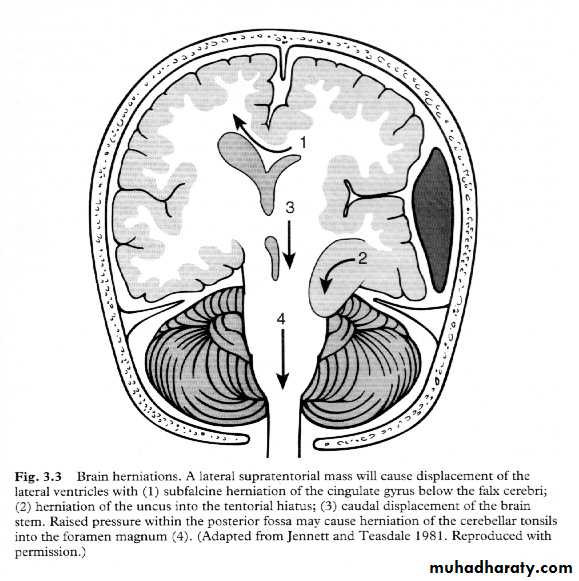

Cerebral Herniation

a. Subfalcine Herniationb. Uncal Herniation

c. Tentorial Herniation

d. Tonsillar Herniation

c. Transtentorial Herniation

d. Foramen magnum herniation(Tonsillar Herniation)

d. Foramen magnum herniation

a. Subfalcine Herniation